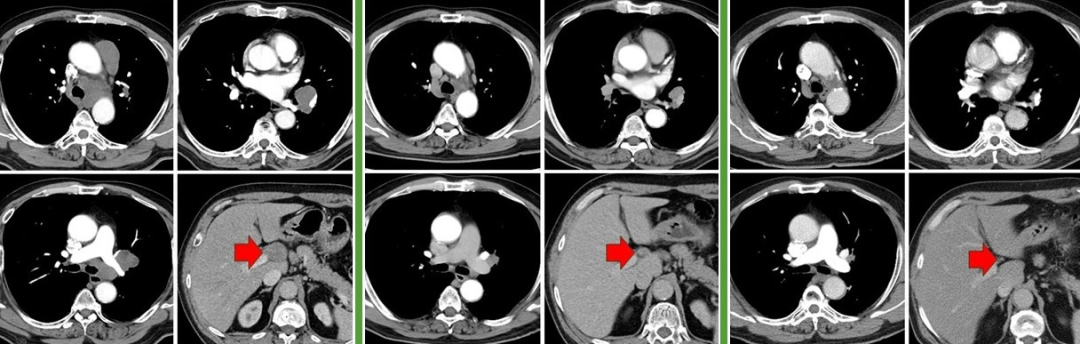

图:左起依次为基线、免疫联合化疗4周期后、末次随访

图:左起依次为三线治疗前、三线治疗后、四线治疗前、末次随访